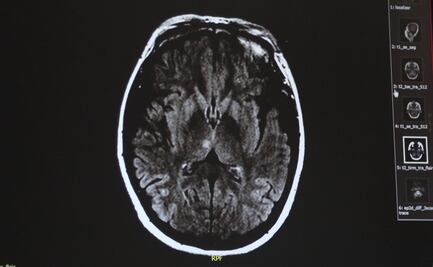

La distorsión del tiempo que experimentamos en un momento placentero o desafortunado se debe a la reacción fatigada de las neuronas cerebrales conocidas como “giro supramarginal”